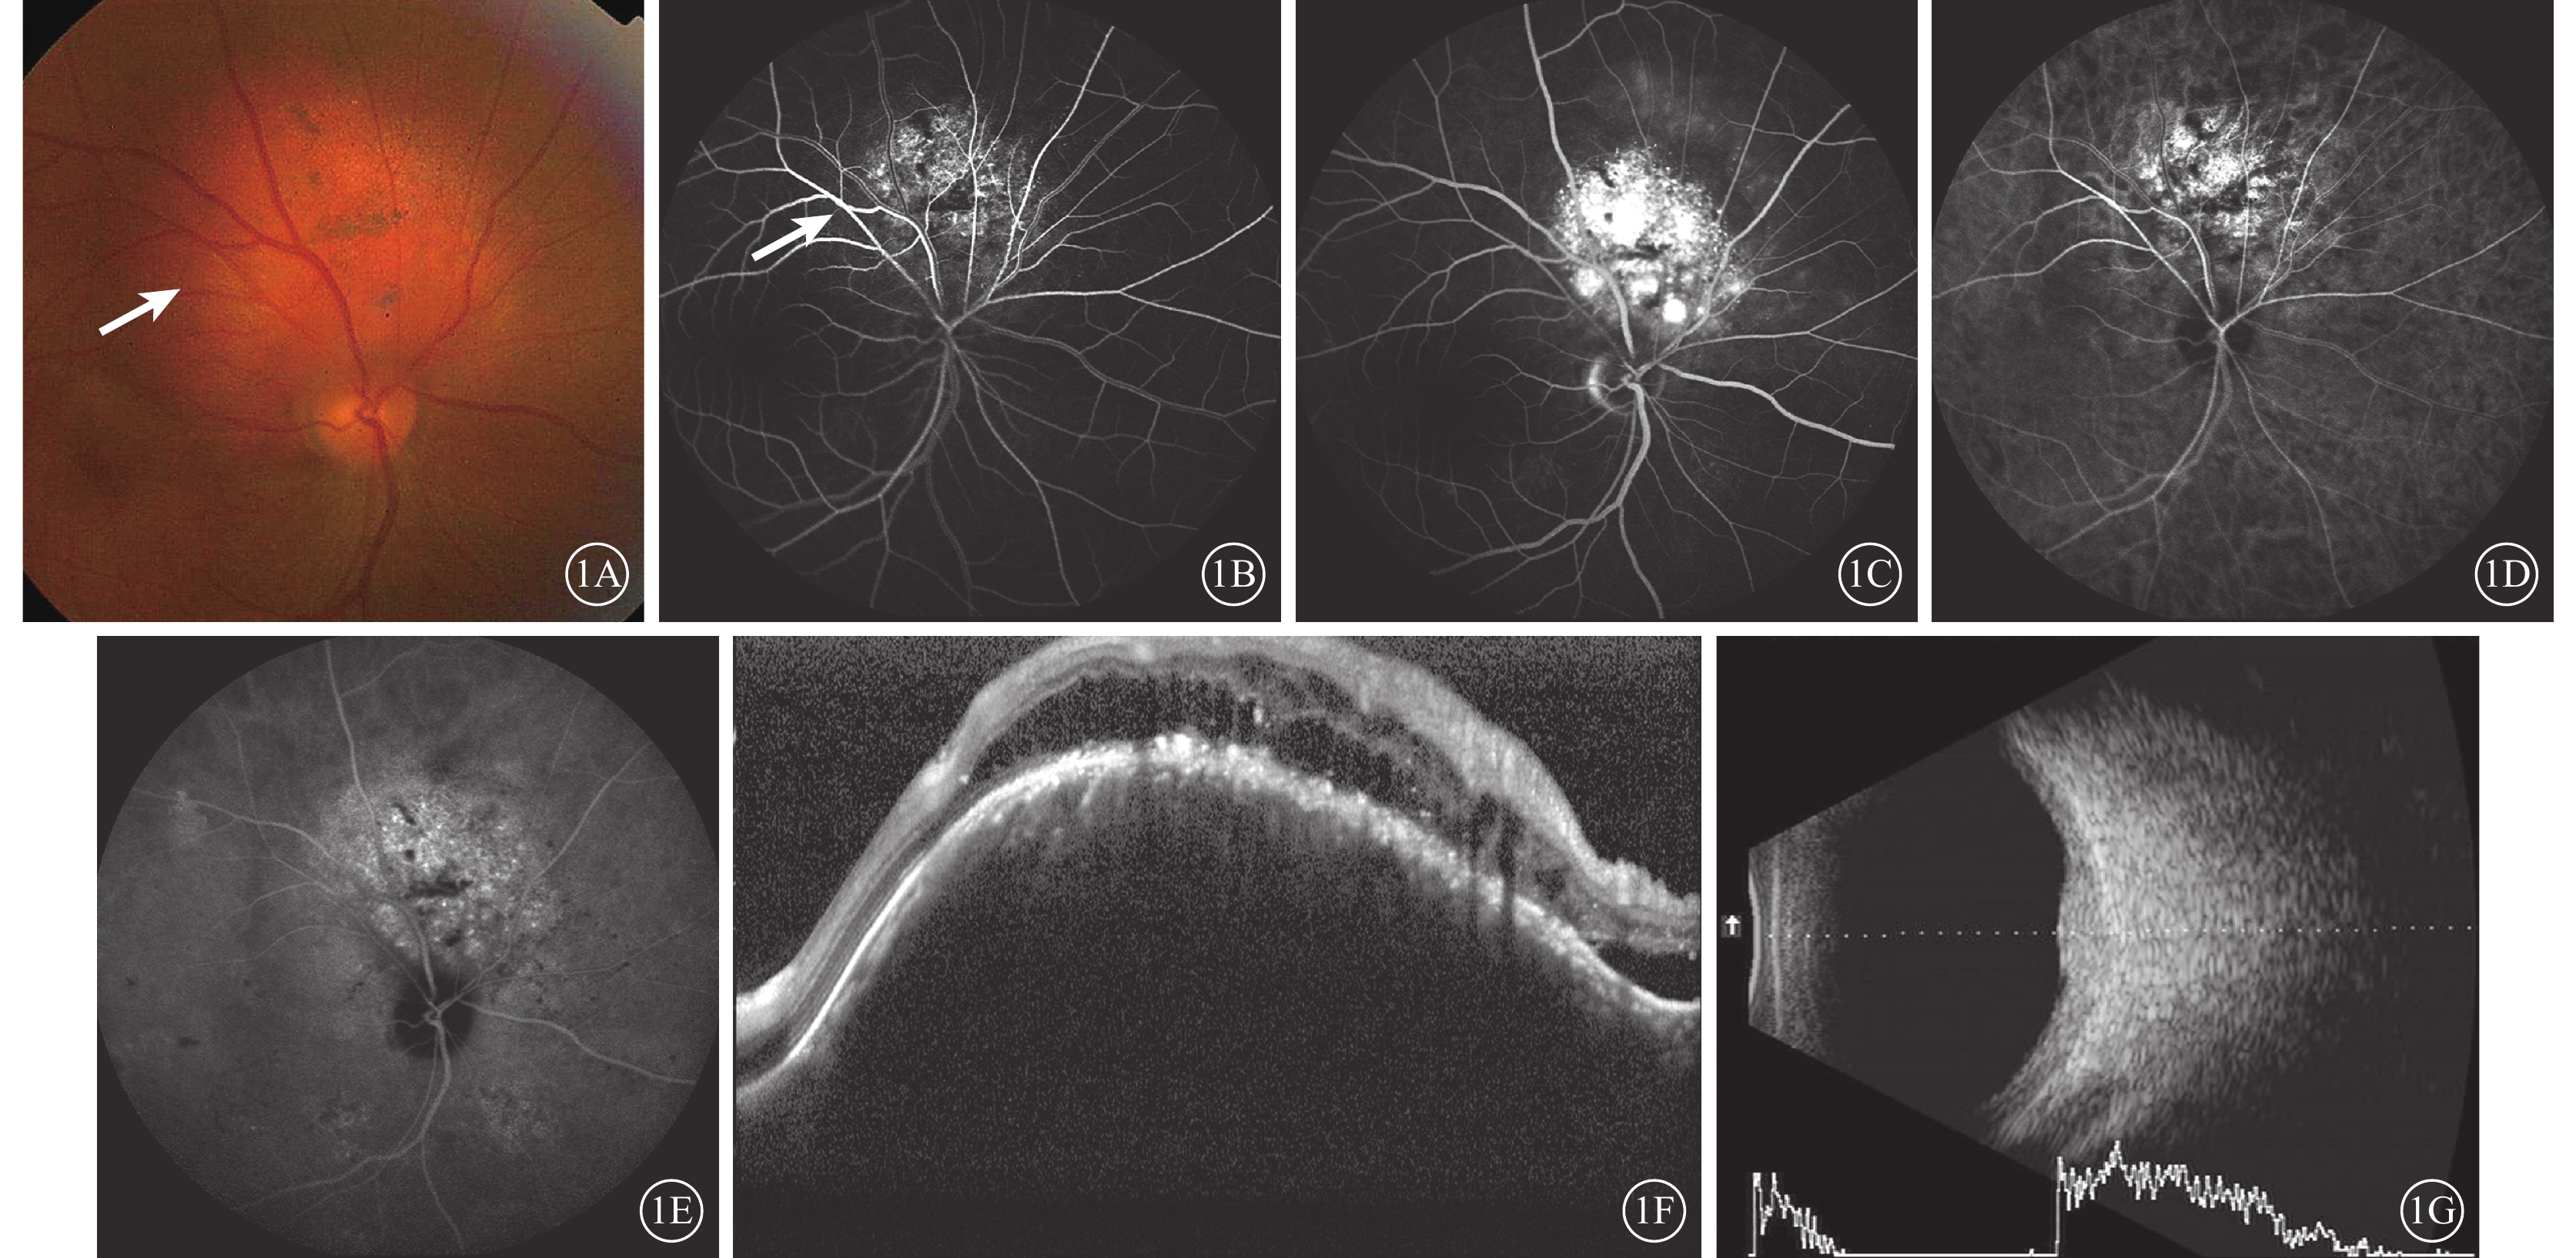

所有患眼瘤體均位于后極部,呈橘紅色隆起、邊界清楚(圖1A);瘤體表面可見色素沉著或黃白色纖維沉著。其中,瘤體位于后極部、視盤鼻上方分別為16、2只眼。FFA檢查,早期瘤體呈斑駁樣強弱熒光夾雜并迅速呈強熒光滲漏,其間散在色素遮蔽熒光;晚期滲漏增強(圖1B,1C)。ICGA檢查,早期瘤體呈網狀強熒光且滲漏逐漸增強;晚期熒光稍沖刷呈“桑椹”狀外觀(圖1D,1E)。頻域OCT檢查,瘤體處視網膜全層隆起,神經上皮層增厚,層間劈裂形成并伴有局限性淺脫離(圖1F)。B型超聲檢查,眼球壁局限性扁平狀實質性隆起病灶;聯合A型超聲檢查,可見瘤體始波為高波,內部回聲均勻一致(圖1G)。